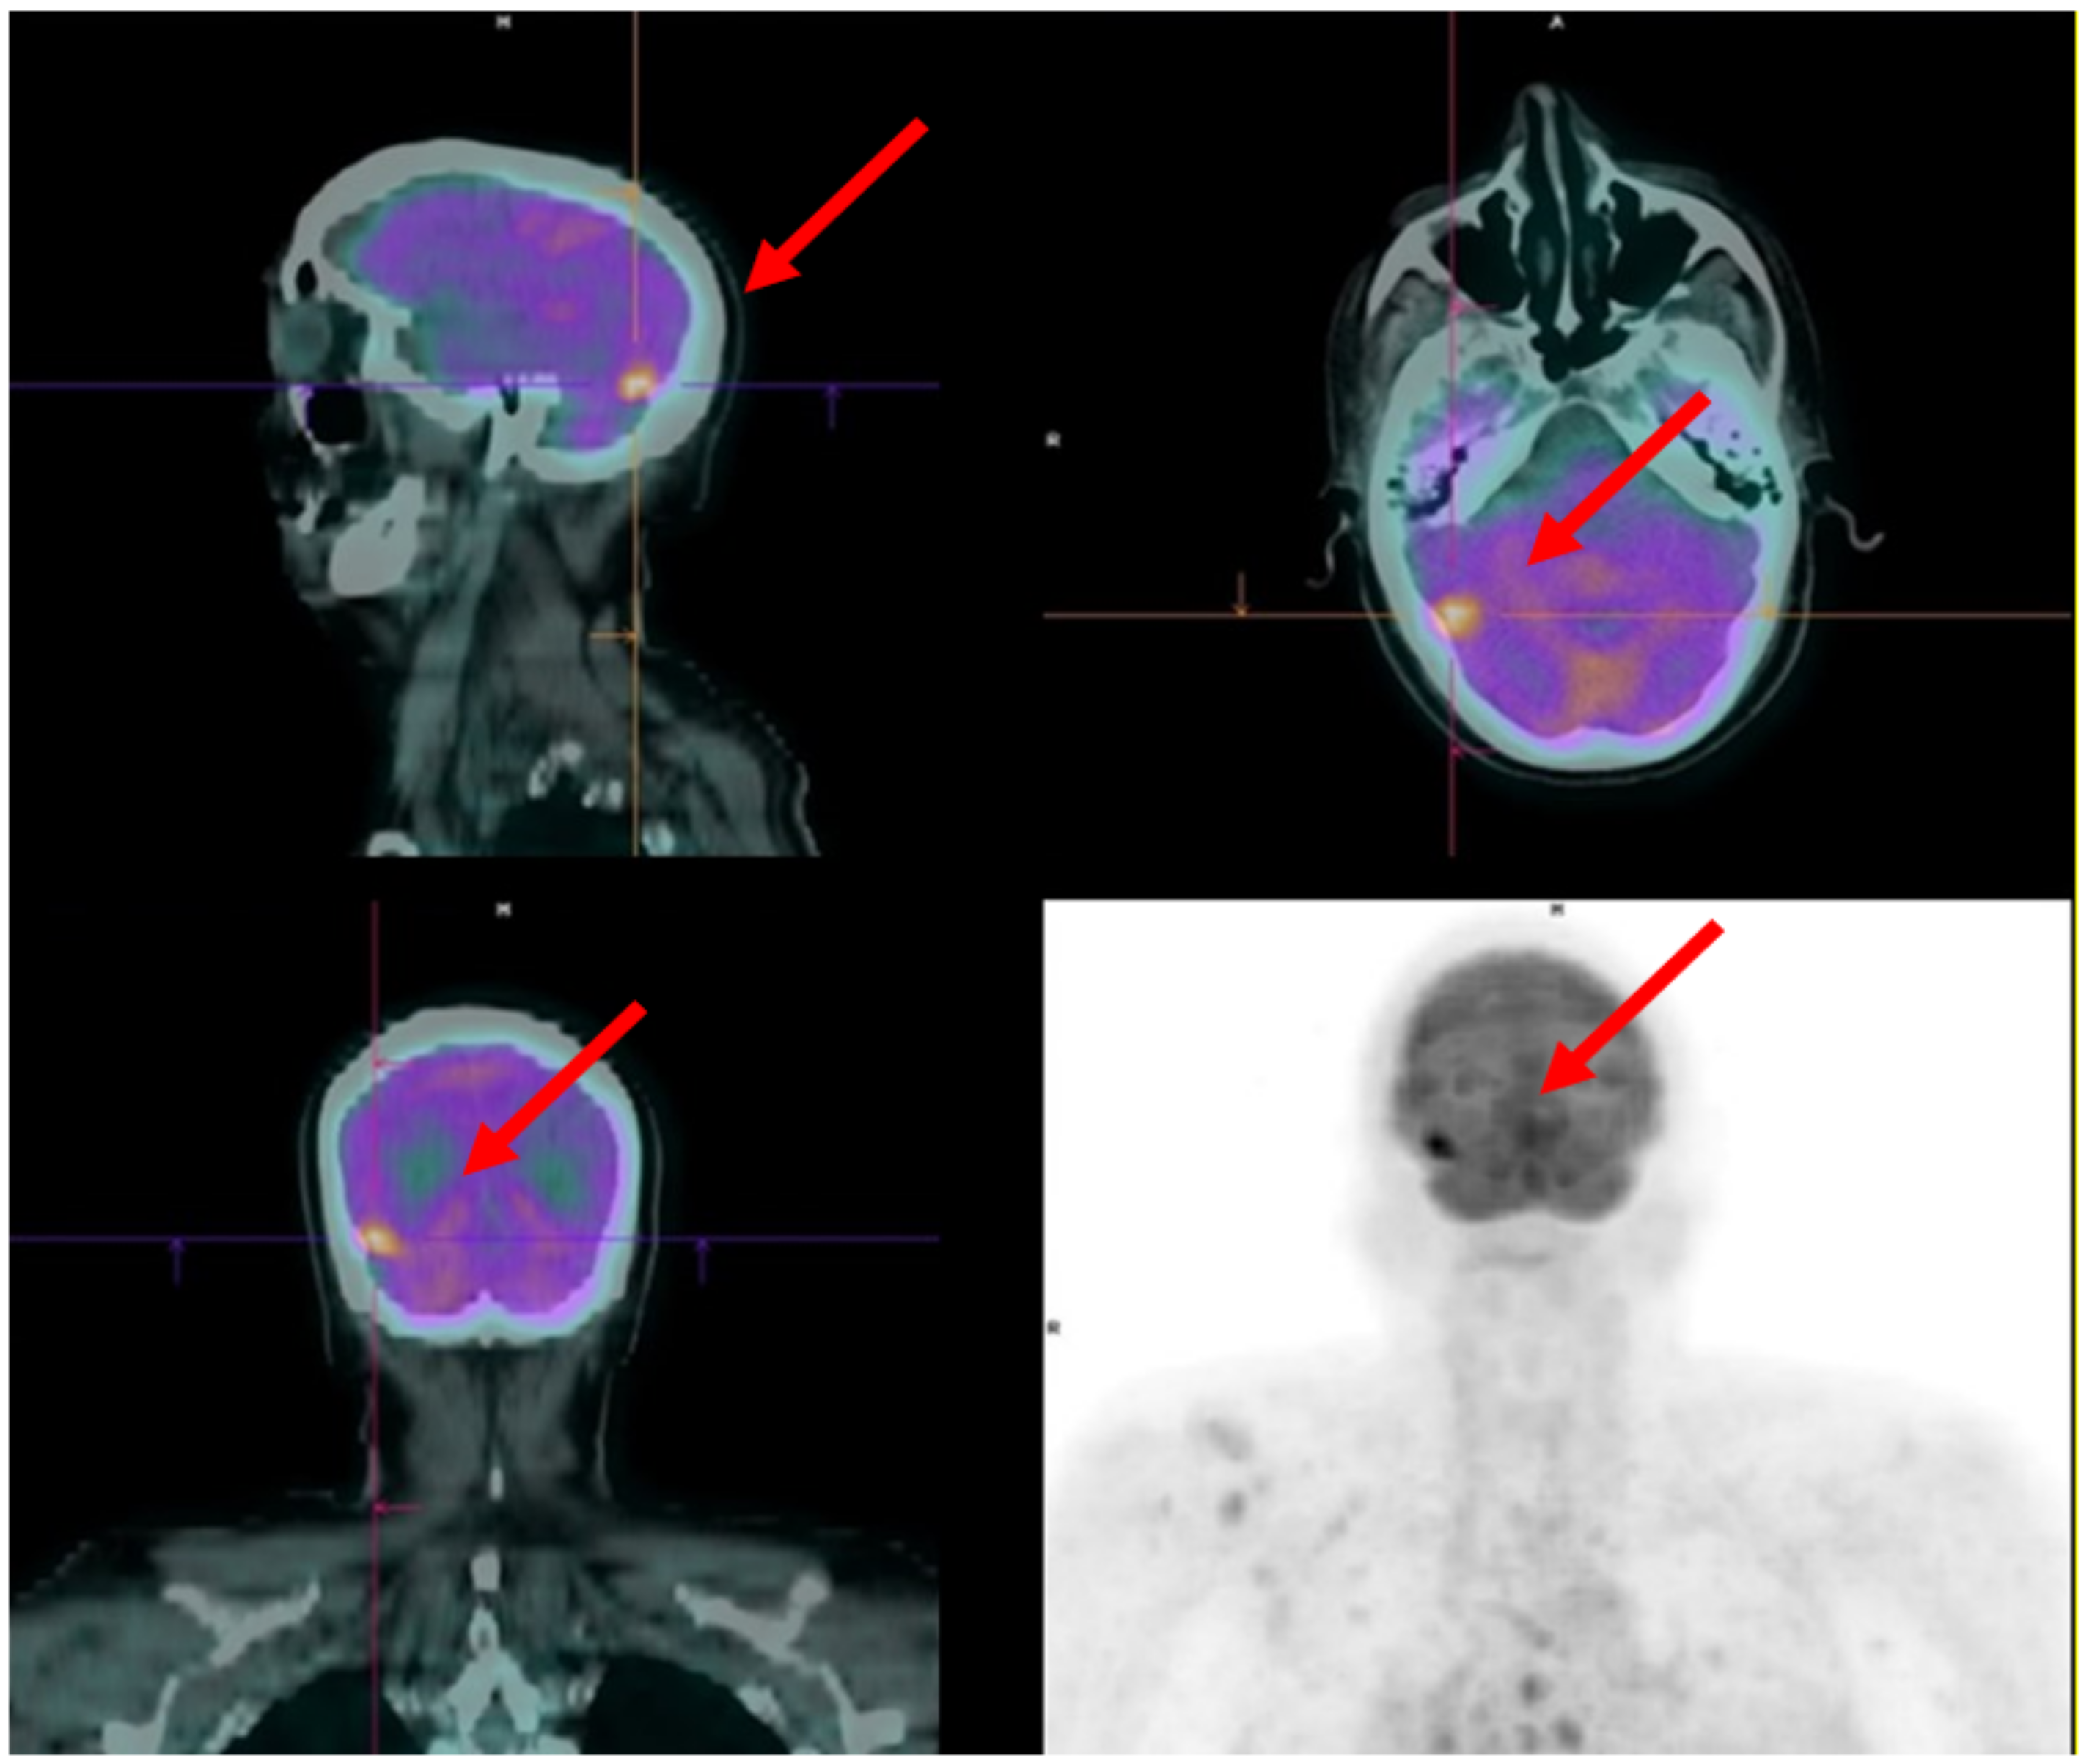

4. FDG PET as a Tool to Improve Systemic Treatment Selection in the Castration-Resistant Phase of the Disease

4.1. Case 1

4.2. Case 2

- Spratt, D.E.; Gavane, S.; Tarlinton, L.; Fareedy, S.B.; Doran, M.G.; Zelefsky, M.J.; Osborne, J.R. Utility of FDG-PET in clinical neuroendocrine prostate cancer. Prostate 2014, 74, 1153–1159. [Google Scholar] [CrossRef]

- Bauckneht, M.; Morbelli, S.; Miceli, A.; Rebuzzi, S.E.; Fornarini, G. Neuroendocrine Differentiation of Prostate Cancer Is Not Systematically Associated with Increased 18F-FDG Uptake. Diagnostics 2021, 11, 468. [Google Scholar] [CrossRef]